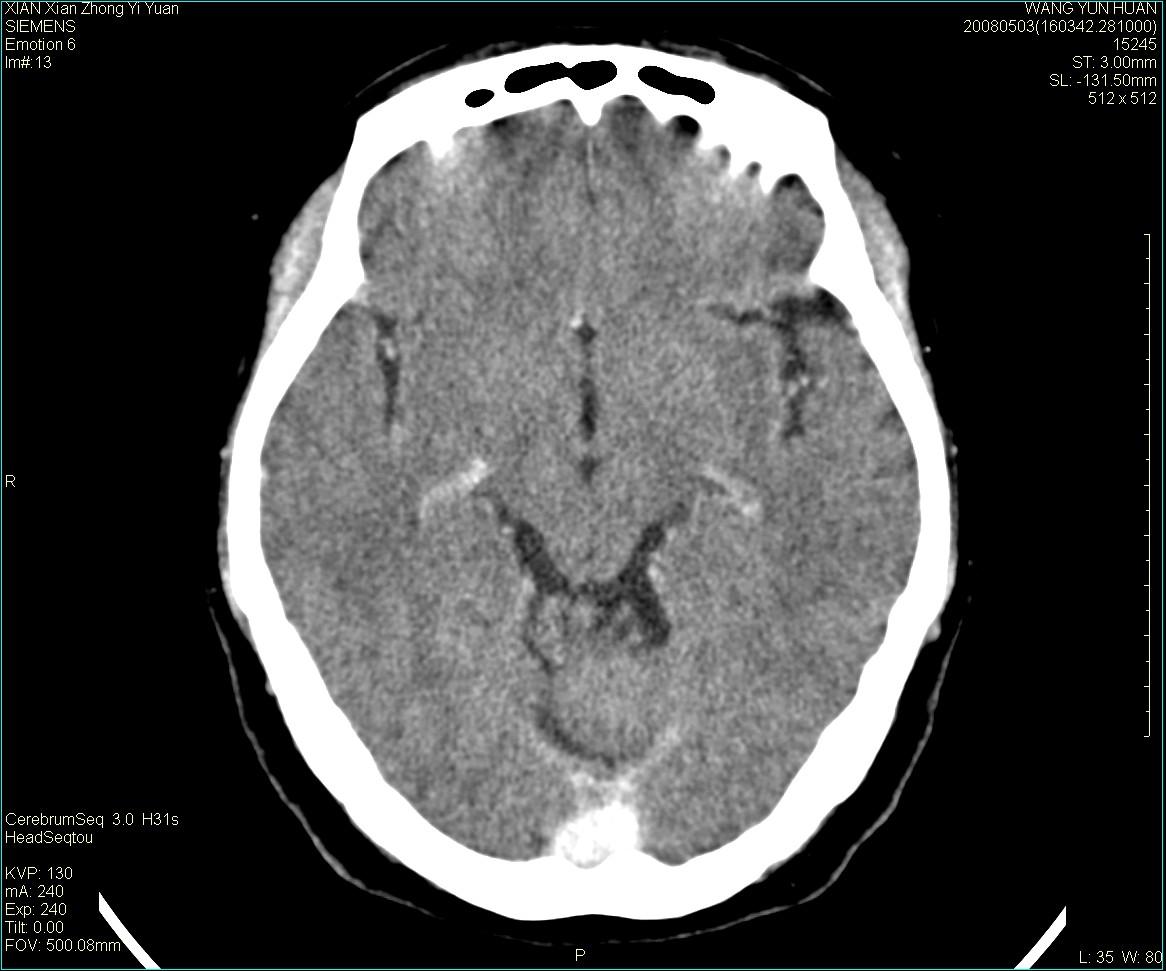

病灶显示轻度强化,ct增加4hu左右,大家看是什么肿瘤.

强化后动脉期及延迟2分钟,五分钟图像

小脑蚓部囊型肿块,内有实性结节及钙化点。增强后囊壁及结节轻度强化。

考虑蚓部星形细胞瘤(ⅱ级可能性大)。

小脑蚓部肿块,周围无明显占位效应及水肿带,增强轻度强化,考虑低分级星形细胞瘤。